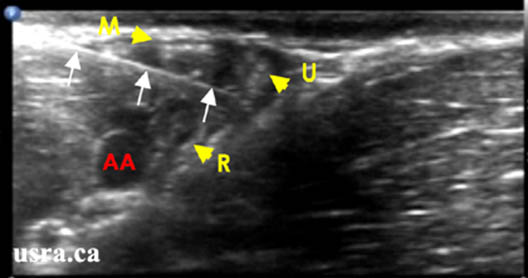

- Considerable anatomic variation is noted for all the terminal branches of the brachial plexus; however the most common orientations are shown in Figure 5.

- Median Nerve – anterior lateral to the artery (above and slightly left, at the 10 to 12 o’clock position relative to the artery)

- Ulnar Nerve – anterior medial to the artery (above and to the right, near the axillary vein, 1-3 o’clock position relative to the artery)

- Radial Nerve – posterior medial to the artery (below and to the right, between 3 to 6 o’clock positions relative to the artery)

- Musculocutaneous Nerve – optimal imaging requires more lateral positioning of the transducer as it lies within the coracobrachialis muscle or fascia just below the biceps muscle

Figure 5. Sonogram of the terminal nerves in the axilla. (M = median nerve, U = ulnar nerve, R = radial nerve, MC = musculocutaneous nerve

Downloaded with permission from Ultrasound for Regional Anesthesia (2008)

Figure 7. In-plane view of a needle positioned between the ulnar (U) and the radial (R) nerves. Note needle relationship to the median (M) nerve and the axillary artery (AA)